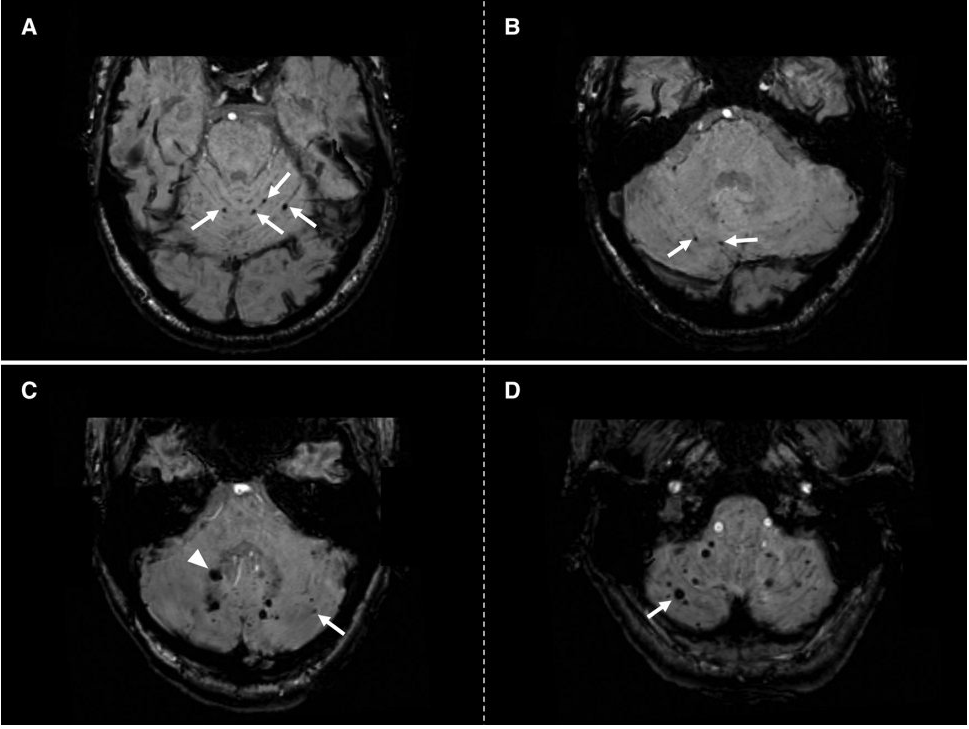

Pannelli A e B: mostrano un paziente con microemorragie cerebellari strettamente superficiali (frecce).

Pannelli C e D: mostrano un pattern misto di CMB cerebellari in un paziente con ICH non correlata alla CAA.

Pannello C: CMB cerebellari localizzate nella sostanza grigia e bianca profonda del cervelletto (punta di freccia) e nell’area superficiale (freccia).

Pannello D: ulteriori CMB nell’area superficiale del cervelletto (freccia) nello stesso paziente.